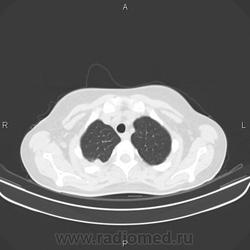

Задействован весь сегмент S2 справа. Полость деструкции. Перисциссурит. Можно сказать, ограничено со всех сторон плеврой. Мелкоочаговие высоко- и среднеинтенсвные тени в S1, S3 и S6 - отсев. Симптом позитивной воздушной бронхограммы. Объективных данных мало, но это инфильтративный туберкулёз сегмента S2 правого легкого в фазе распада и дессименации.

Спасибо всем ещё раз. Описывая КТ нашел ещё отсев в S1,3,6,10 правого легкого и S3,6 левого легкого. Так что туб этиология вызывает все меньше сомнений.

Больше данных за инфильтративный туберкулёз с распадом и обсеменением, но всё-таки абссцедирующую пневмонию из диф.ряда я бы не убирал, т.к. ни в одном из очагов не вижу признаков пресловутого казеоза( вкраплений извести).Было бы хорошо, если бы вы предствили R-граммы 2-недельной давности, кстати отсутствие по ним динамики, на фоне антибактериального лечения ещё не доказывает туберкулёзный процесс, т.к. есть пневмонии с затяжным течением и может быть прогрессирование пневмонии на фоне лечения. Необходима консультация фтизиатра.

уплотнение в верхней доле с распадом, односторонними ценрилобулярными узелками,без поражения левого легкого-сомнительно сразу писать tbc,включить бронхиолит,атипичную пневмонию,грибковое поражение (аспергиллез) в д.д ряд